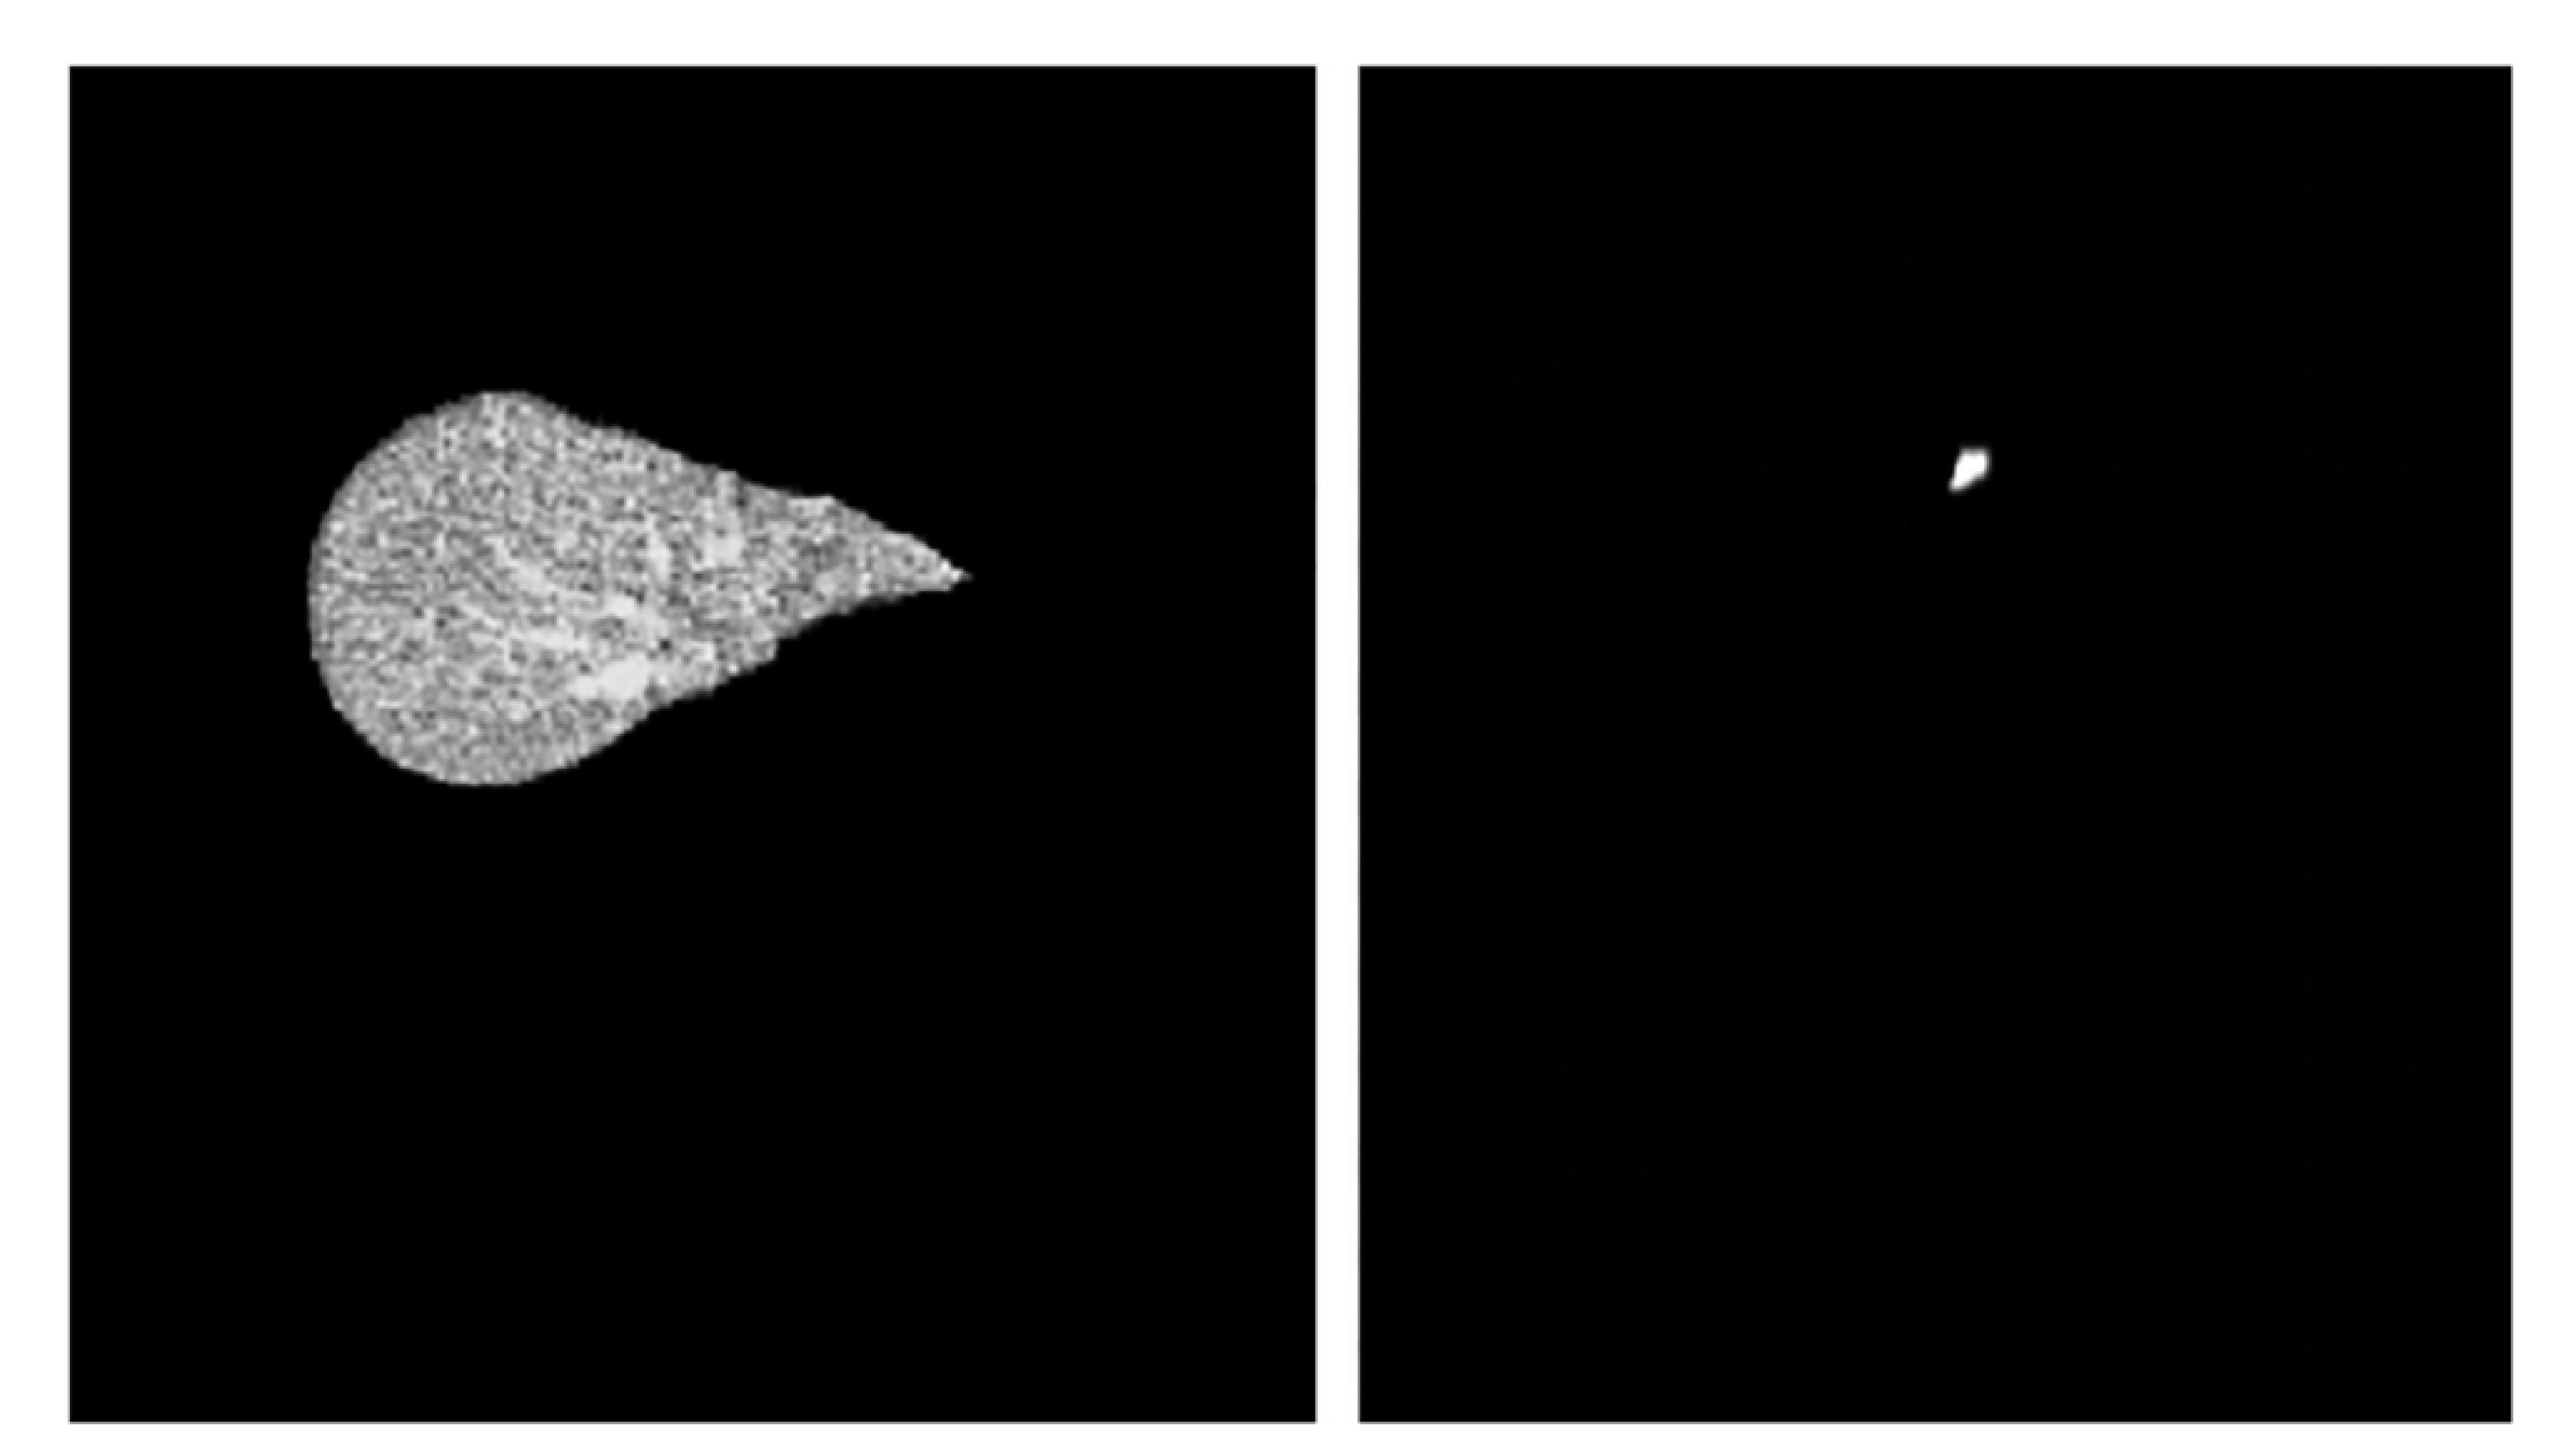

3.1. Dataset Selection

3.2. Data Augmentation